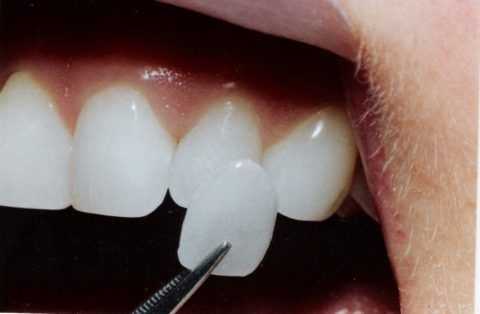

В случае если пациент хочет быстро избавиться от патологии глубокого перекрытия, то врач может предложить зафиксировать виниры. Однако данная процедура не устраняет причину заболевания и потому носит только временный характер.